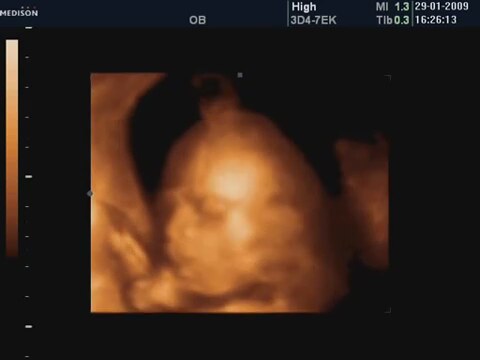

20 Haftalık Bebeğin 4 Boyutlu Ultrasın Görüntüsü